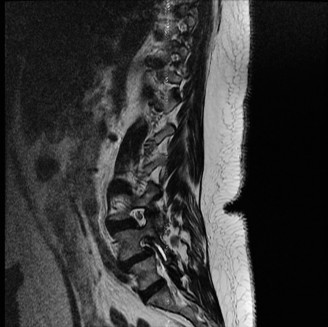

Upon his return five years later, the imaging profile was drastically different. Standing lateral radiographs now revealed a Meyerding Grade 2 spondylolisthesis at L5-S1, indicating that the L5 vertebral body had translated anteriorly by 25% to 50% over the sacral promontory. Furthermore, there was a noticeable collapse of the L5-S1 intervertebral disc space, signifying advanced degenerative changes secondary to the altered biomechanics and chronic instability. We also meticulously measured the patient's spinopelvic parameters on a standing 36-inch scoliosis cassette. His Pelvic Incidence (PI) was measured at 65 degrees (high), which mathematically dictates a higher Sacral Slope (SS) and Pelvic Tilt (PT). A high PI is a known biomechanical risk factor for the progression of spondylolisthesis, as it creates a steeper lumbosacral shear angle, placing immense anterior translational force across the compromised L5-S1 segment.

To evaluate the neural elements and the soft tissue structures, a comprehensive MRI of the lumbar spine without contrast was obtained. The T2-weighted sagittal and axial sequences confirmed the Grade 2 anterolisthesis and demonstrated severe bilateral foraminal stenosis at L5-S1. The exiting L5 nerve roots were severely compressed between the hypertrophied, fibrocartilaginous pseudarthrosis tissue of the pars defect dorsally, and the bulging, degenerated L5-S1 disc and superior endplate of S1 ventrally. Furthermore, the MRI revealed Modic Type II changes (fatty replacement of the subchondral bone marrow) in the adjacent vertebral endplates, confirming chronic biomechanical stress and discogenic degeneration. The central canal remained relatively patent, which is characteristic of isthmic spondylolisthesis, as the posterior neural arch is left behind during the anterior translation of the vertebral body.

Clinical & Radiographic Imaging Archive